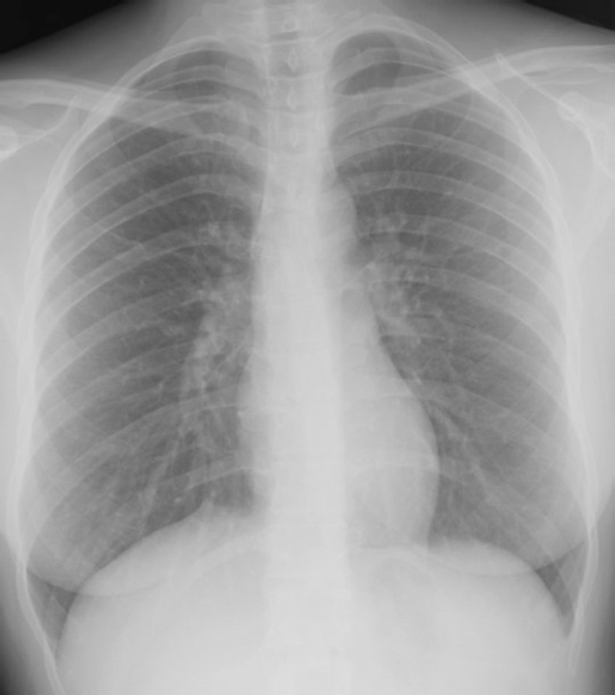

The second problem is that everything kind of looks the same, but what is “normal” for one patient could actually be a harbinger of certain, horrible death in another. How to tell the difference is totally beyond my puny, small brain. Here is an example:

Background Ground Rule for Reading X-rays #1: White things in the lung? Probably not a good thing. LOOK AT THESE LUNGS! They are covered in white! The lungs are supposed to look basically black. Air looks black. Because, you know, science.

So obviously this is a horribly diseased lung and this person is about to keel over dead from some sort of horrible asbestos-induced disease. Or maybe a out-of-control fungus. Let’s look at the caption for this photo:

Well, sh*t.